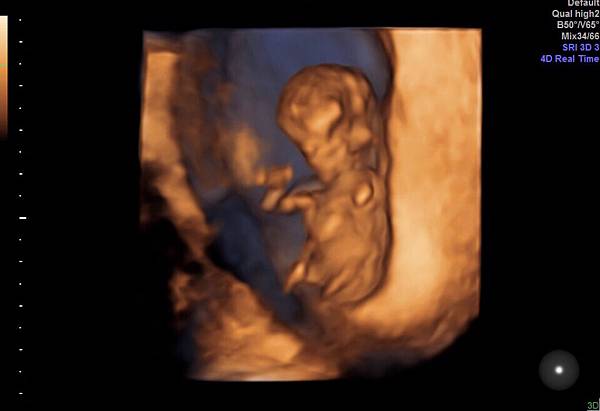

終於聽到護士叫我的名字,照慣例要先照超音波確認寶寶的健康;護士以為我是來確認心跳的,當我告知已經11週他一直微笑說「不好意思,那從肚子照就好了啦」。跟醫師說因為是做試管,現在比較穩定後要轉到婦產科做產檢,陳星佑醫師真的就跟照片一樣,非常~和藹,是我很喜歡的醫師的感覺,讓我們看了寶寶也聽了心跳,還看了3D,第一次看到立體的寶寶,好可愛,一樣很活潑好動的舞動著。確認寶寶後就是確認我有沒有不舒服,告知孕吐很嚴重,醫師開了止吐藥和消脹氣的藥,醫師說止吐藥需要時吃,不用擔心會影響寶寶,因為吐反而會讓腹部用力更不好。另外也告知一些自費的檢查,例如測D3是否足夠,NIFTY+檢測(還在跟R討論到底要做穿刺還是抽血),子宮癲癇症(但因為我有阿斯匹林過敏,所以醫師在意若驗出來為高危險群,一般是使用阿斯匹林控制,但我就只能觀察,所以希望檢查出來沒問題。

附上檢查後的幾張影像,和一張外星人的3D照。